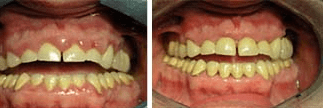

Resolución de la inflamación tras el tratamiento periodontal para el cuidado de las encías sangrantes

Otro caso de desinflamación de encías sangrantes